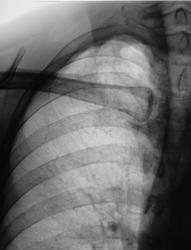

Взяли на контроль, смутили очаги на верхушке.

Они и меня смущают.

.... и меня тоже))))...причем и левая тоже))))- очаговая тень на фоне 1-го ребра и немного за него выступающая....

а что с ключицей? подскажите!!!

Была сломана, срослась...не это главное))))